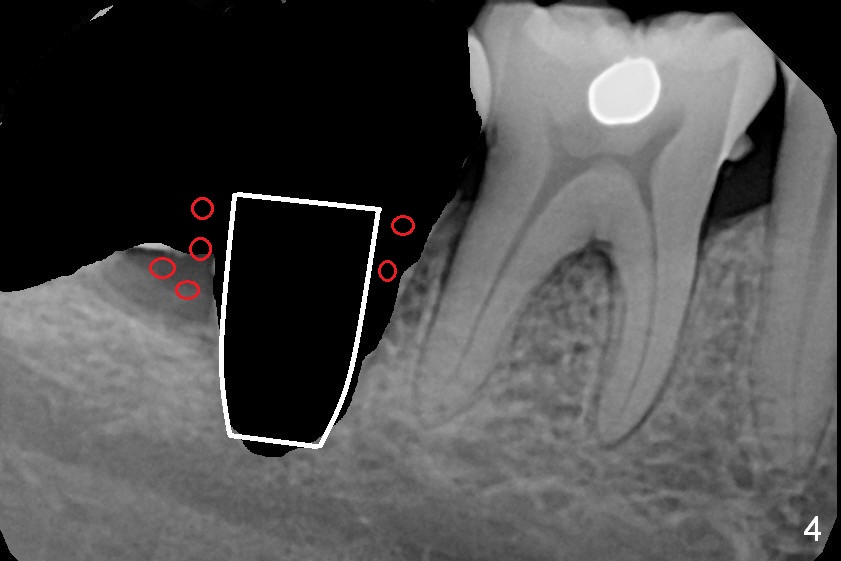

A 39-year-old woman has pain and mobility associated with the tooth #31 (Fig.1 (taken 5 months earlier), 2). It is easy to extract the mesioangularly impacted third molar (#32) after extraction of #31. After debridement and Clindamycin socket disinfection, collagen plug is placed in #32 socket, while allograft in the bottom half of the #31 one. The most coronal portion of the sockets are packed with mixture of collagen and Osteogen plugs and fixed in place with 4-0 Chromic gut (Fig.3). Two or 3 months postop, use #15 to start bone expansion at #31, followed by osteotomes or bone expanders and Tatum tapered taps. Take preop X-ray for depth measurement. The socket is close to the Inferior Alveolar Canal. In one word, no drill will be used for osteotomy. Place bone graft (Fig.4 red circles) prior to implant placement (white outline). Take CT post implant placement to confirm that the Inferior Alveolar Nerve is lingual to the implant.